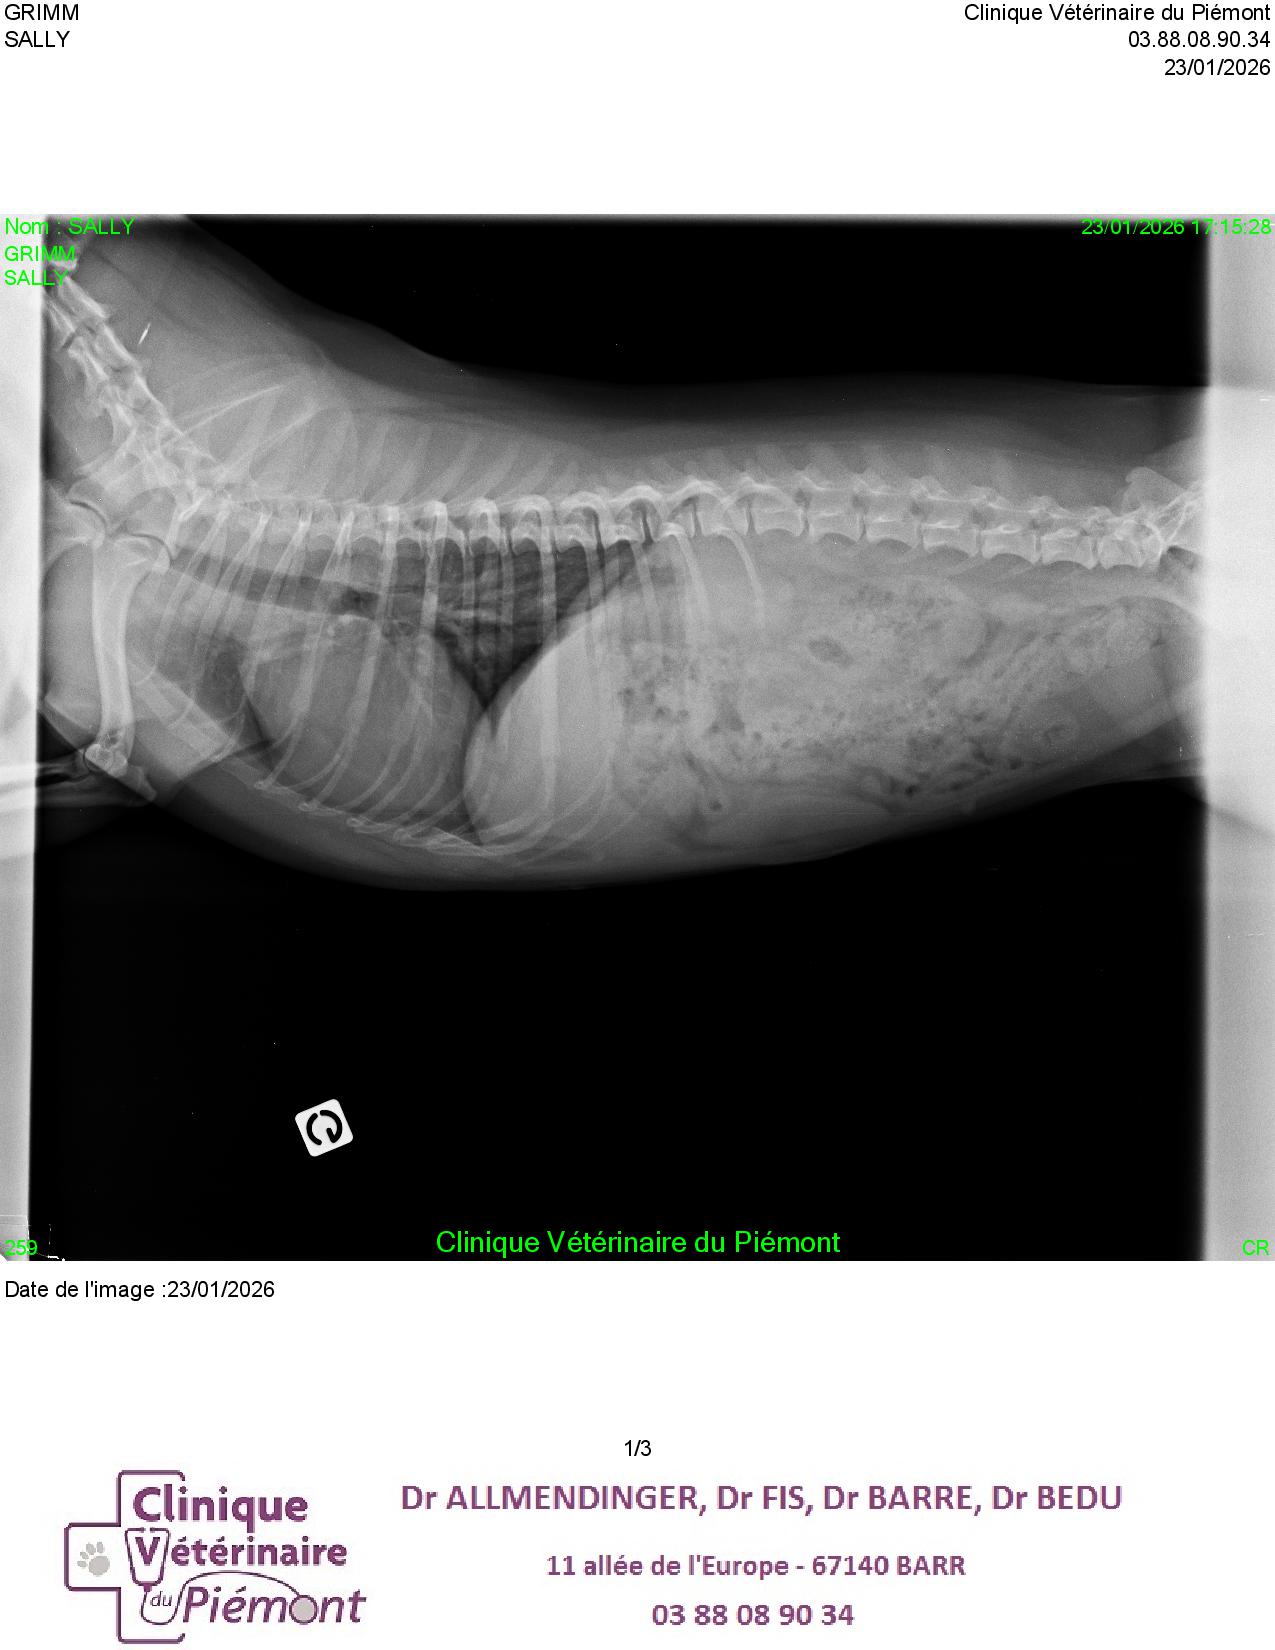

- Connaître les principaux examens à considérer chez un chien présenté en dyspnée aigue

- Connaître les limites de l’examen échographique pour l’exploration d’une dyspnée aigue chez le chien